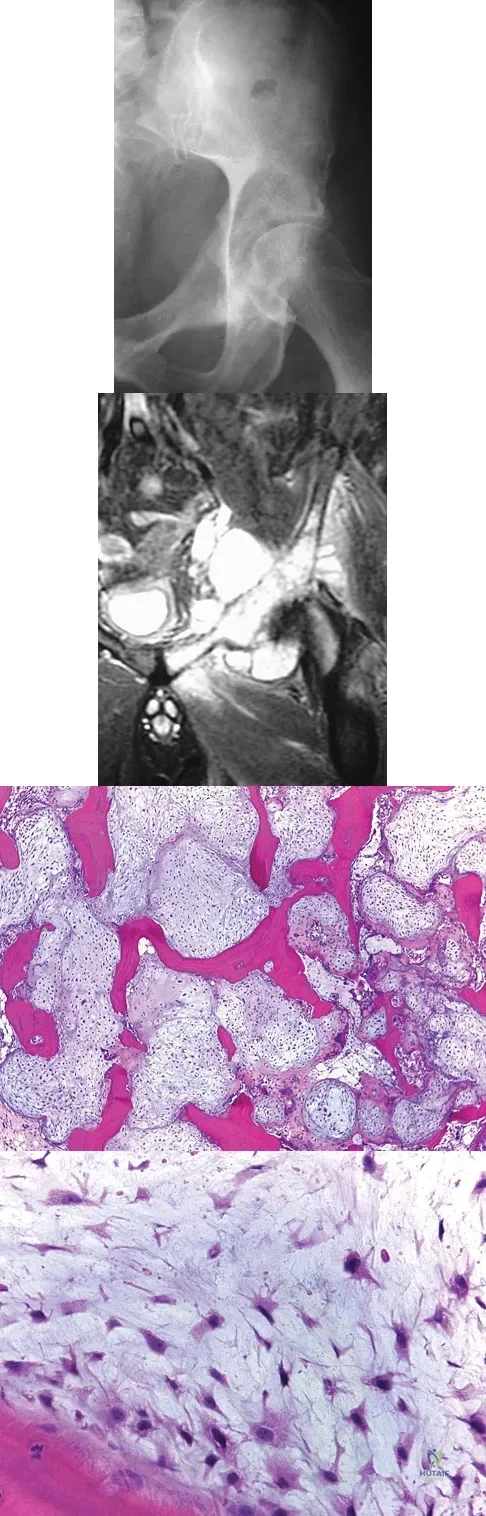

A 10-year-boy has had thigh pain for the past several months. He denies any history of trauma. Examination reveals no soft-tissue mass, and mild tenderness. Figures 33a and 33b show the plain radiograph and MRI scan, and the biopsy specimens are shown in Figures 33c and 33d. What is the most likely diagnosis?

Explanation